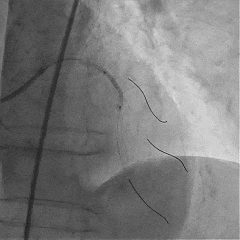

交换工作导丝至LAD远端

预扩球囊依次扩张LAD近中段病变处,造影可见远端血管显影,导丝位于真腔。

于LAD近中段植入Tivoli 2.75*33mm支架一枚,高压球囊后扩张后,血流TIMI3级

Sion导丝至LCX远端,预扩球囊扩张后,植入支架XIENCEAlpine 2.25*23mm支架一枚

术后造影支架膨胀良好,血流TIMI3级